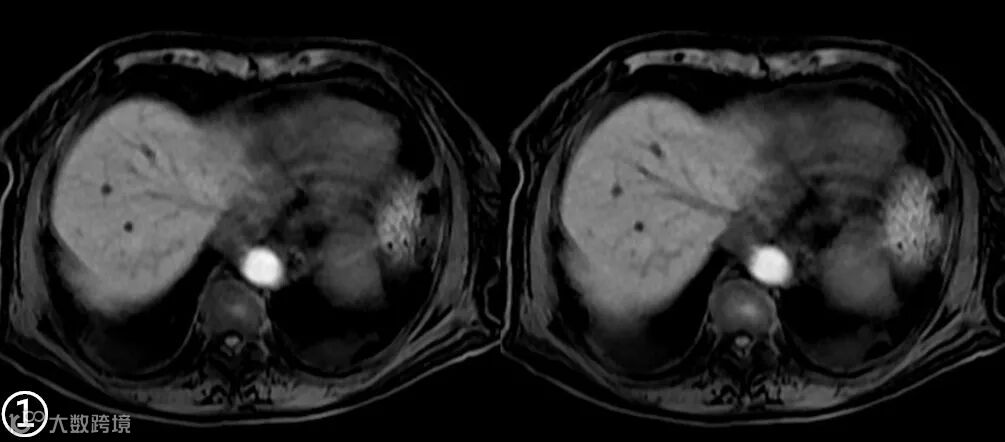

MRI图像上的组织信号与诸多因素相关,如序列、参数、组织本身的状态等。所以应首先要看是什么序列,使用的什么参数,目标组织的状态是怎样的。 -

MRI上的信号是相对的,没有绝对的高与低,而要看与谁比,在解读MRI图像信号时要选取信号相对稳定的组织作为参照对比,如肌腱,脑脊液。 -

在增强机理方面,MRI“对比剂”与CT“造影剂”有着本质的区别。钆对比剂本身并不会产生信号,而是当钆对比剂与水分子的距离足够近时,通过缩短周围水质子的T1弛豫时间来间接产生“增强”的作用。切记不要以信号强度的高低来判定摄取对比剂浓度的多少。